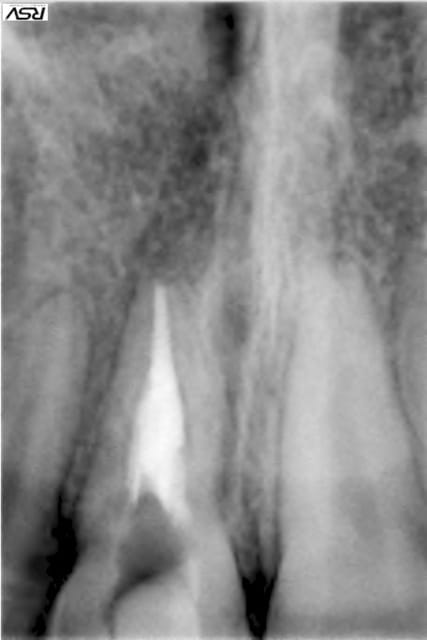

1° CAS une belle perf traitée avec du Biodentine. Résultat à 2 ans.

2°CAS expulsion - réimplantation immédiate - à 3 ans résorption interne - biodentine . le résultat est sans commentaire.

voilà les photos

1 hlkygf - Eugenol

2 jvxkl9 - Eugenol

3 owbzxu - Eugenol

6 alrbjd - Eugenol

3 iwmo8e - Eugenol